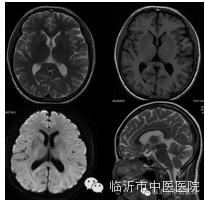

对颅脑组织的对比度增加,能更清晰的显示解剖结构和病变组织,尤其DWI成像使得对病变组织的显示更敏感。

常用于超急性脑梗塞的诊断与鉴别诊断,有利于尽早挽救可逆性缺血性坏死脑组织,针对指导临床治疗具有重要的意义。

在脑肿瘤术前诊断,术前评估肿瘤特征,指导术者及术后评测肿瘤切除效果等方面有着广泛的临床应用价值。

磁共振波谱是分子成像技术,主要用于癫痫、肿瘤及梗塞的诊断与鉴别诊断。